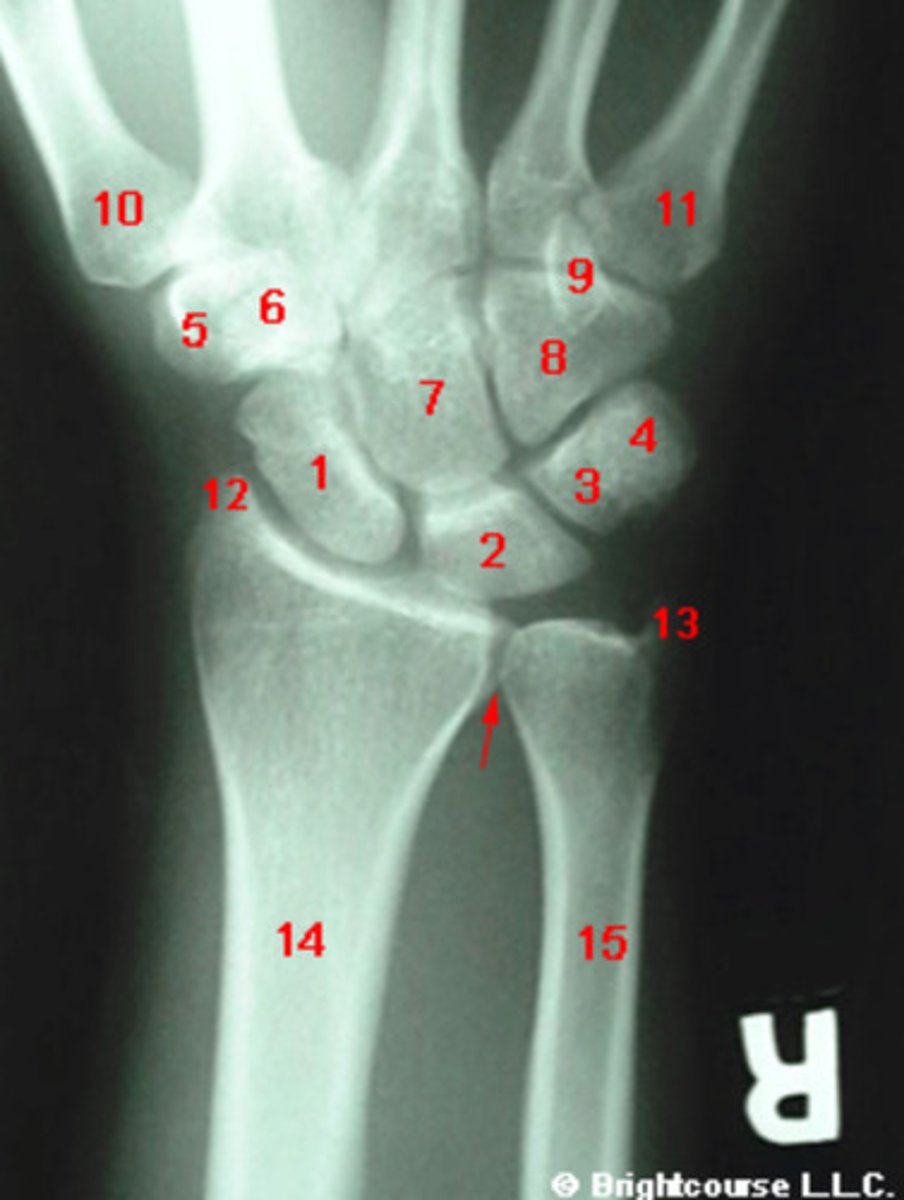

PA, internal oblique, and lateral

What are the standard plain film radiographic projections for the wrist?

Capitate

What structure is indicated by number 7?

Scaphoid

What structure is indicated by number 1?

Lunate

What structure is indicated by number 2?

What is the most commonly fractured carpal bone?

Triquetrum

What structure is indicated by number 3?

Pisiform

What structure is indicated by number 4?

Trapezium

What structure is indicated by number 5?

Trapezoid

What structure is indicated by number 6?

Hamate

What structure is indicated by number 8?

Styloid process of ulna

What structure is indicated by number 13?

Styloid process of radius

What structure is indicated by number 12?

Hook of the hamate

What structure is indicated by number 9?

Base of the first metatarsal

What structure is indicated by number 10?